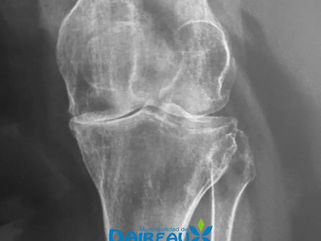

SE REALIZÓ EL PRIMER REEMPLAZO PARCIAL O UNICOMPARTIMENTAL DE RODILLA EN EL HOSPITAL MUNICIPAL DE DAIREAUX

Por primera vez, se llevó a cabo en el Hospital municipal de Daireaux el primer reemplazo parcial o unicompartimental de rodilla....